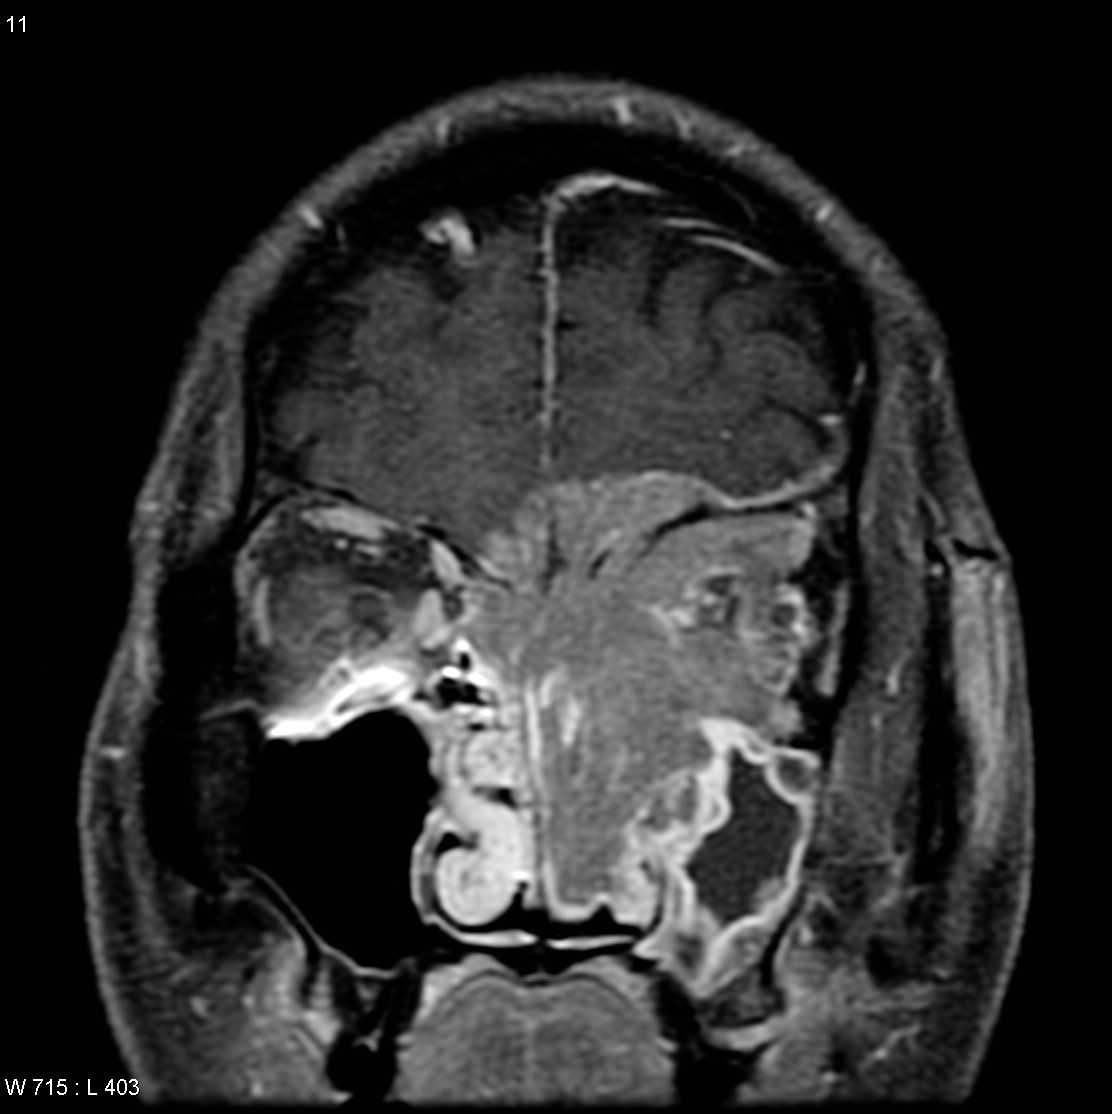

Le carcinome indifférencié sinonasal (SNUC) est un cancer rare de la cavité nasale et / ou des sinus paranasaux. Les premiers symptômes de cette maladie comprennent un saignement de nez, un écoulement nasal, une vision double, des yeux gonflés et une obstruction nasale.

Le traitement se compose de traitement combinés chirurgicaux, de radiothérapie et de chimiothérapie.